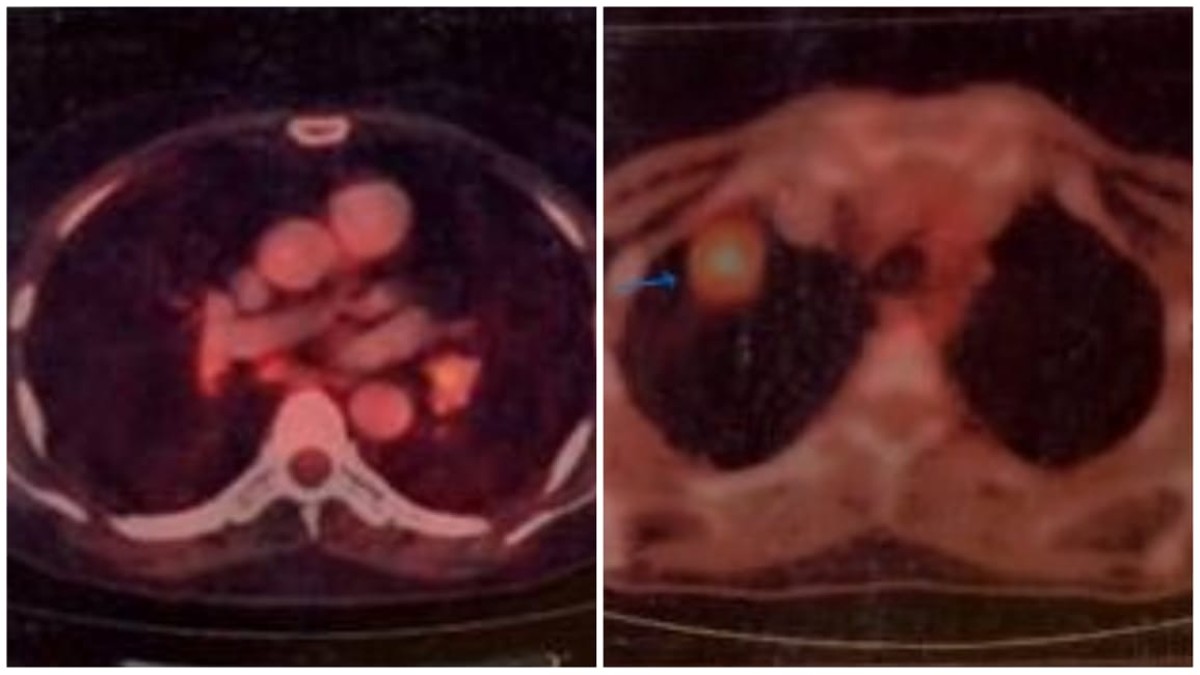

एम्स भोपाल का रेडियोथेरेपी विभाग इम्यूनोथेरेपी का उपयोग करके कैंसर के दो रोगियों का सफलतापूर्वक इलाज किया है, जिसमें एक स्टेज 4 फेफड़ों के कैंसर और दूसरा स्टेज 4 ग्रासनली कैंसर शामिल था। डॉक्टर्स के अनुसार मरीजों को पूरी तरह से राहत मिली।

एक महत्वपूर्ण विकास में, एम्स भोपाल का रेडियोथेरेपी विभाग इम्यूनोथेरेपी का उपयोग करके उन्नत चरण के कैंसर वाले दो रोगियों का सफलतापूर्वक इलाज किया है। दोनों मामले, एक स्टेज 4 फेफड़ों के कैंसर और मस्तिष्क मेटास्टेसिस के साथ और दूसरा स्टेज 4 ग्रासनली कैंसर के साथ जो पारंपरिक उपचारों के लिए प्रतिरोधी है, इम्यूनोथेरेपी की क्षमता को प्रदर्शित करते हैं।